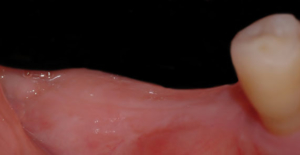

Impiantolo, dapprima triste e solo, fu invece pian piano avvicinato e abbracciato da tanti nuovi amici: globulino rosso, globulino bianco, piastrina, connettivina, collagenina e tanti altri che lo circondarono di tanto affetto e lo considerarono uno di loro, così che lui si poté sentire finalmente perfettamente integrato!!! …aveva finalmente compreso il suo vero talento.